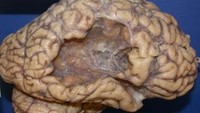

Contoh otak pasien yang selamat dari stroke. Meski dirinya bisa bertahan hidup namun kerusakan sudah terjadi terbukti dari sebagian otak yang hilang. Pasien diketahui meninggal karena sebab lain. (Foto: neuropathology-web.org)